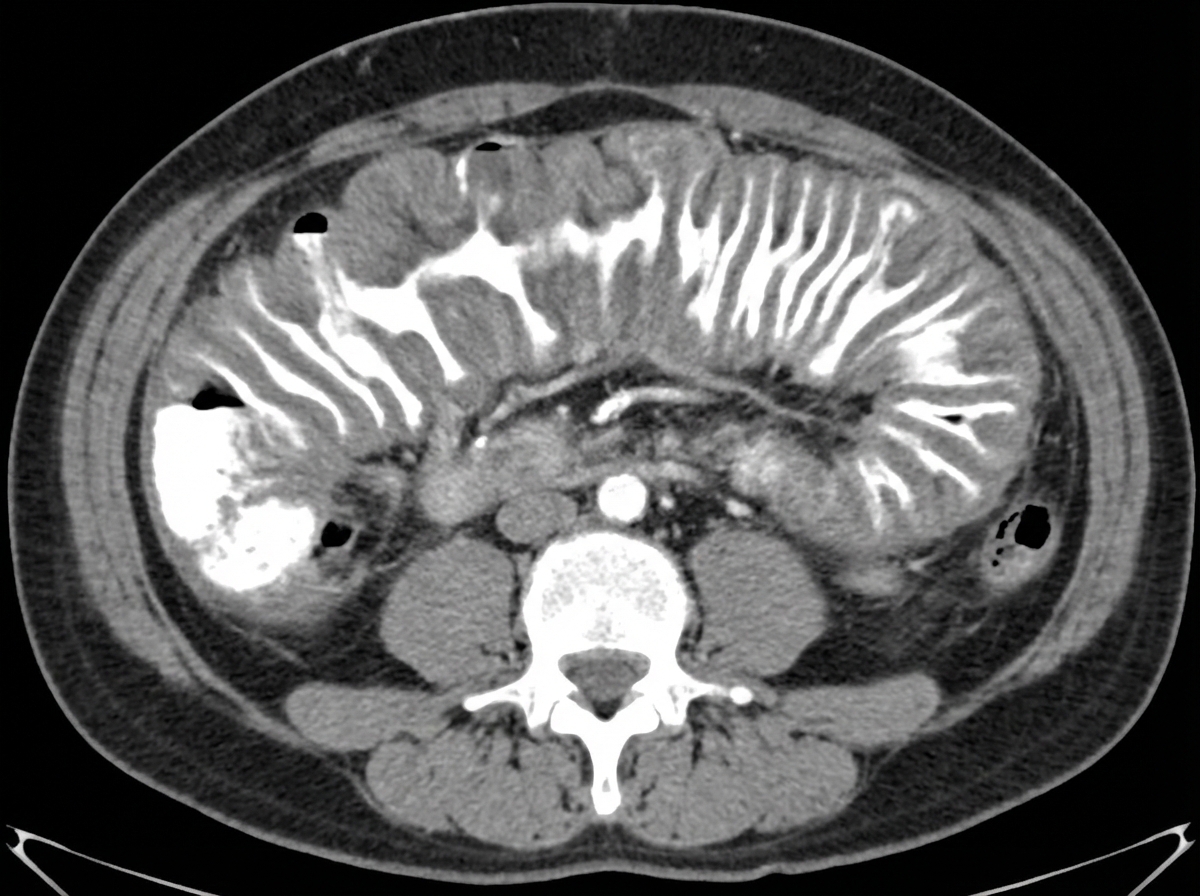

A 40-year-old male presented with watery diarrhea. Stool cytotoxin assay was positive. Colonoscopy revealed ulcers, plaques, and pseudomembranes. The patient's condition improved significantly with metronidazole. The provided CECT shows a characteristic sign. What is the name of this sign seen on CECT?

Explanation: ***Accordion sign*** - The **accordion sign** on CECT represents **oral contrast trapped between thickened, edematous haustra** in **pseudomembranous colitis**, creating alternating bands of high and low attenuation resembling an accordion. - This sign is **pathognomonic for C. difficile colitis** and correlates with severe mucosal inflammation and **pseudomembrane formation** seen on colonoscopy. *Central stellate scar* - This is a characteristic finding of **focal nodular hyperplasia (FNH)** of the liver, showing a **central fibrous scar** with radiating septa. - It has no association with **colonic pathology** or **C. difficile infection**. *Whorl sign* - The **whorl sign** is seen in **intestinal volvulus**, particularly **sigmoid volvulus**, showing a **twisted bowel loop** with a characteristic spiral appearance. - It indicates **mechanical bowel obstruction**, not infectious colitis with **pseudomembrane formation**. *Honeycombing* - **Honeycombing** is a **pulmonary imaging finding** seen in **end-stage pulmonary fibrosis**, showing clustered cystic spaces in subpleural regions. - It is completely unrelated to **gastrointestinal pathology** and **C. difficile colitis**.